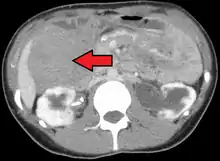

Desmoid tumor as seen on CT scan

MRI or CT imaging scans are commonly used for monitoring.[45][1]